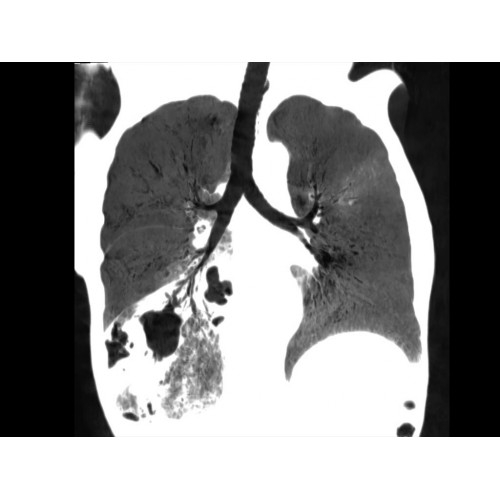

Позволяет проводить комплексные исследования всех анатомических зон, включая нейровизуализацию, ангиографию, исследования органов грудной и брюшной полости. Особенно эффективен для раннего выявления онкологических заболеваний.

Специализированные исследования